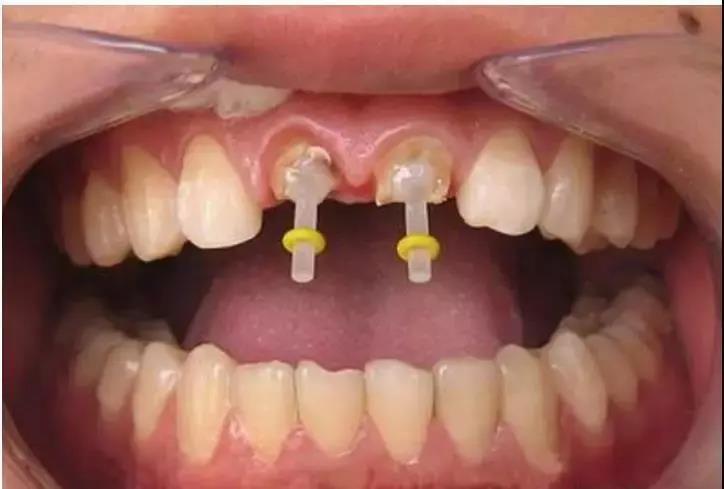

一些人在进行根管治疗后,会进行牙齿打桩。牙齿打桩是指在患者牙齿缺损较大,或因为外伤等原因只剩下牙根时,因剩下的牙齿过短或力量过于薄弱,不能用修复体直接修复,需要给牙根里打桩,加固并延长折断的牙齿,以使假牙能获得足够的力量固定。下面口腔专家给大家具体介绍一下牙齿打桩的相关知识。

牙齿打桩是指插入根管内的部分,利用摩擦力和粘固力、粘接力获得固位,进而为最终修复体提供固位。

什么样的牙齿需要打桩

1、由于龋坏(虫牙),外伤等原因造成牙冠大面积缺损者;

2、牙齿缺损只剩下牙根,而牙周健康,牙根有足够的长度,经牙龈切除术能暴露出根面者;

3、错位,扭转牙而没有条件做正畸治疗或非正畸适应者。

4、畸形牙,直接磨牙固位不良者。